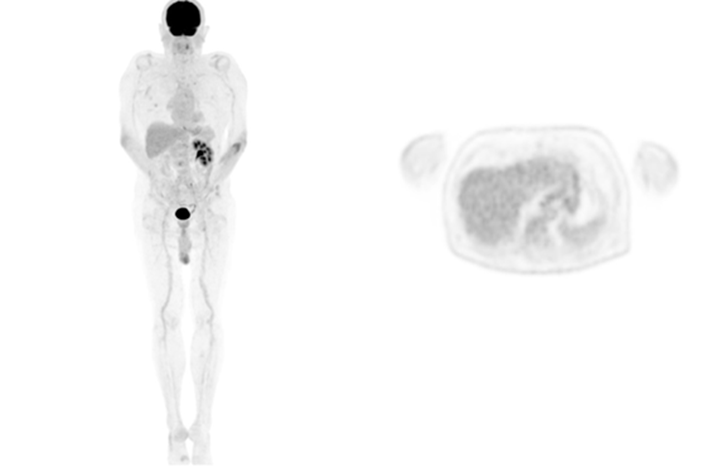

Secondly, in terms of image quality, our team has seen first-hand the major step up from analog to digital cameras and the progressive image improvement with successive iteration of UIH's AI algorithm. This is particularly striking when the same patient returns for their follow-up studies (see Figure 1-3) on the different platforms.

Figure 2. MIP and axial image of the same patient scanned on uMI 550 with HYPER DLR AI PET algorithm (injection dose: 239 MBq of 18F-FDG, 60 min uptake time, scan time: 2 min/bed position)